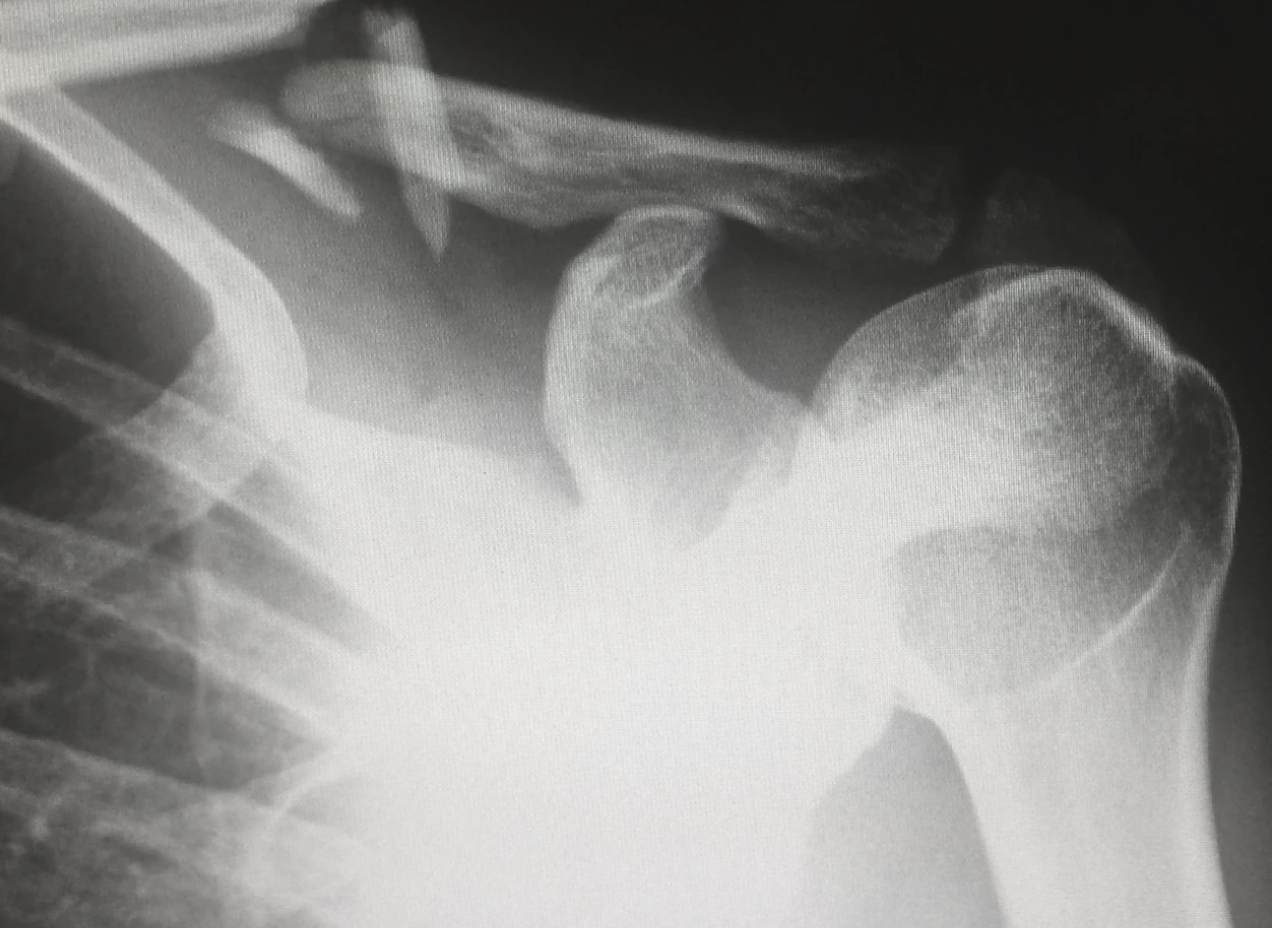

석회화 건염 어꺠 사진. 왜 석회화 건염 환자에게 운동이 중요한가?